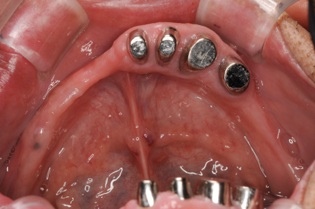

この方は結局、all on 4 を応用し、奥歯に両側2本のインプラントを傾斜埋入して、それにマグネットをつけました。これなら骨移植をせずにインプラントが可能になり、3ヶ月ほどで終了できます。

マグネットをつけているので大幅に義歯の面積を縮小することが可能になりました。